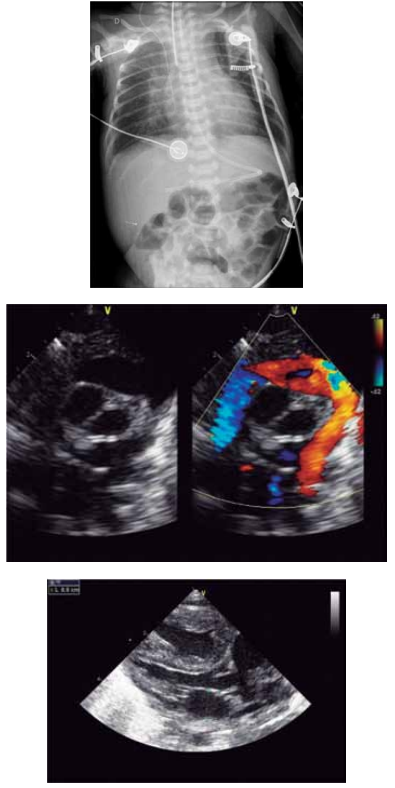

Qual é o diagnóstico provável da cardiopatia congênita ilustrada pela radiografia de tórax e a figura de ecocardiograma apresentadas desse recém-nascido?